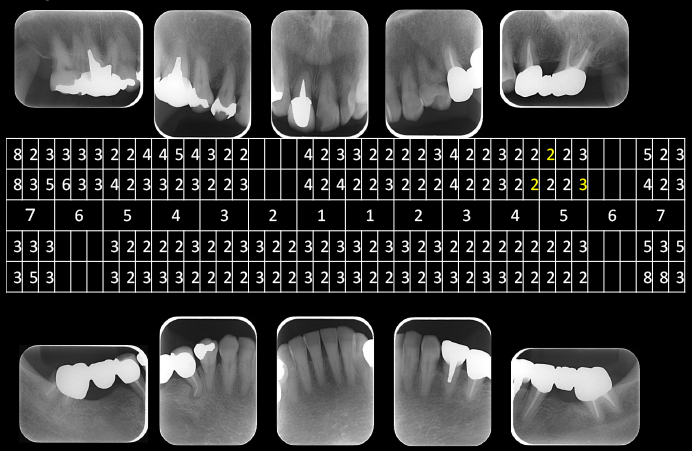

デンタル10枚法及びプロービングチャート

デンタル10枚法及びプロービングチャートです。

全体的には歯槽骨の吸収はみられませんが、左下7は左下8の影響により、遠心部に垂直性の骨欠損がみられます。

右上2から左上1には不十分な根管充填がみられます。

初診時デンタル及びプロービングチャート

右上6番7番右下7、左下7番および左上7番には深いポケットがみられます。

左下7の近心には垂直性の骨欠損を認めます。

X線上では分かりにくいですが右下7には歯根に及ぶカリエスを認め、

また右下5には破折したリーマーと根尖病変を認めました。

右下5番は残念ながら再治療が不可能と判断し抜歯、右下7番もむし歯が進行しすぎているため保存ができないと判断し抜歯としました。